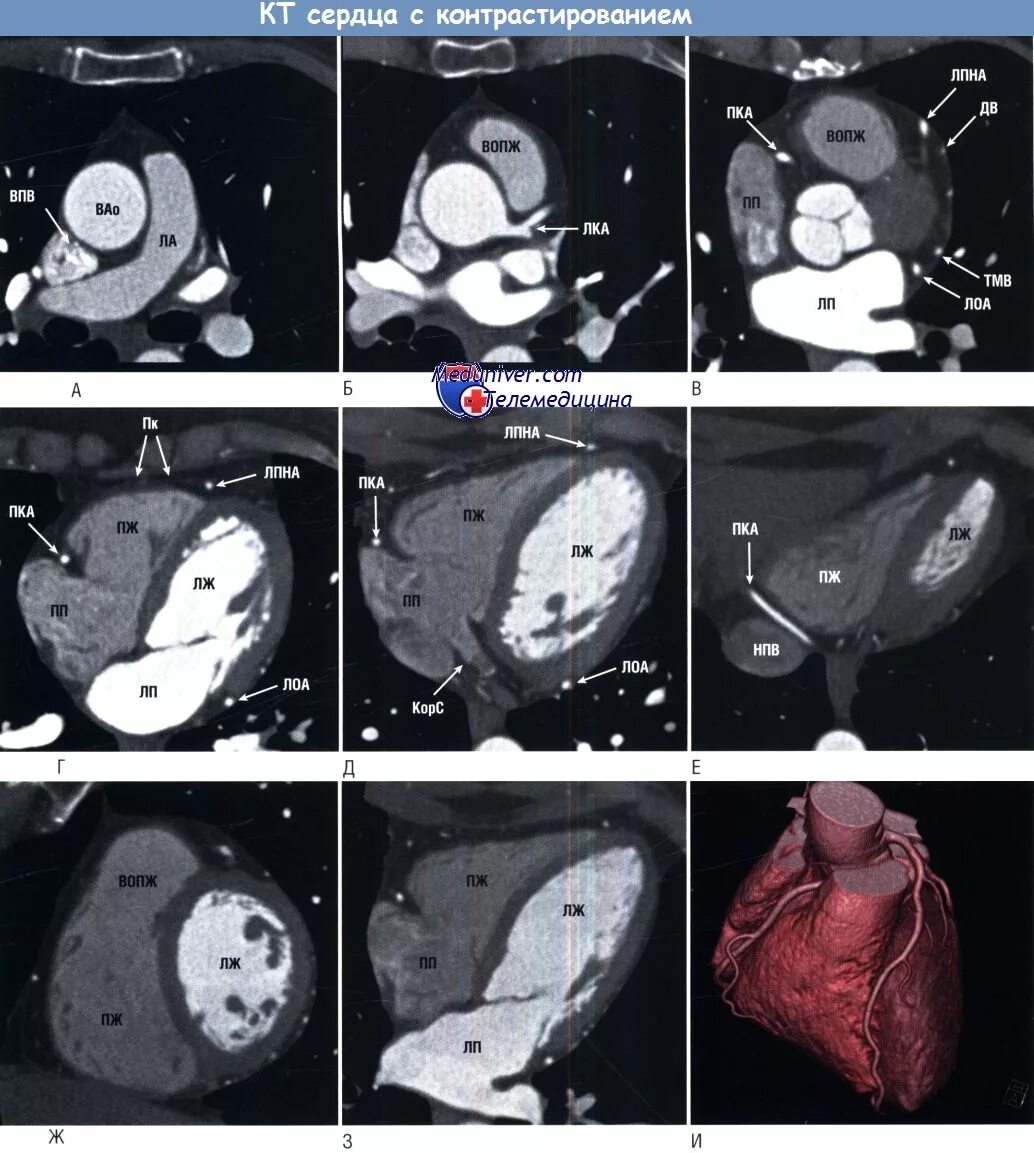

Можно заменить кт на мрт